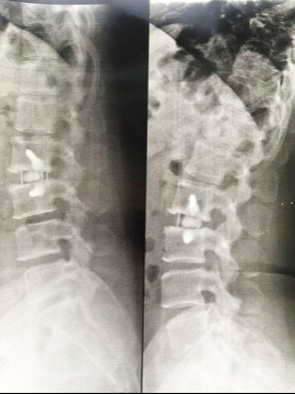

Normalmente, é necessária uma complementação posterior como fixação da coluna por parafusos pediculares de forma percutânea com incisões pequenas e leve afastamento muscular. Diferente da cirurgia posterior tradicional, que são incisões maiores com maior afastamento muscular, que pode causar mais dor no pós-operatório.

Após confirmar o nível da coluna com uso de radiografias é realizada a ressecção do disco doente, que é uma das fontes de dor, o que permite a introdução de maiores próteses (Cages), favorecendo o ganho de altura discal e a abertura do forame neural, que é o espaço pelo qual os nervos saem da coluna, ocasionando a descompressão destes e aliviando as dores radiculares (dores de compressão do nervo).

Como há colocação de maior Cage, promove-se a correção do desalinhamento da coluna e maior estabilidade com maior índice de artrodese da coluna, assim, garantindo melhor correção cirúrgica e um melhor resultado da cirurgia.

Uso de afastadores especiais com remoção do disco doente e colocação de Cages nos espaços discais.